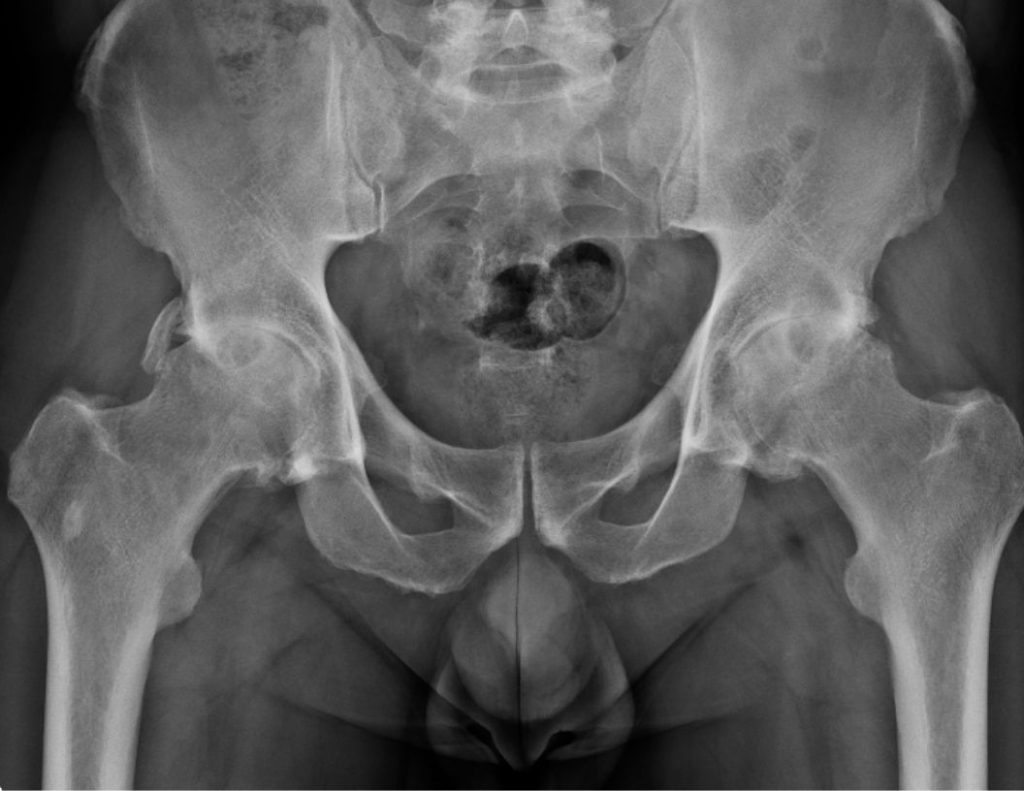

Coxartosi

Prima